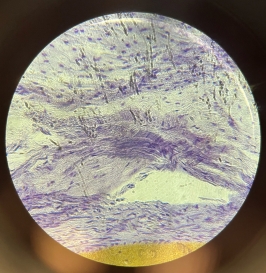

Dense Regular Collagenous Connective Tissue (Fibrous Tissue)